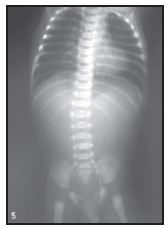

O médico plantonista é chamado ao alojamento conjunto para avaliar RN de 4 horas de vida com história de “engasgar" durante a mamada. História gestacional: GI PI, toxemia leve, parto cesariana por CTG alterada. RN de 38 semanas, PN 3.200g, Apgar 9/10. Na sala de parto foram realizadas secagem e aspiração da vias aéreas superiores. Ao exame, RN eupneico, saturação O2 94% em ar ambiente, com bolhas de muco na cavidade oral e tosse frequente. Abdome plano, sem visceromegalias. A tentativa de passagem da sonda gástrica, esta não progrediu.

Analisando a história, o exame clínico e a radiografia do paciente (indicada acima), o diagnóstico mais provável é: